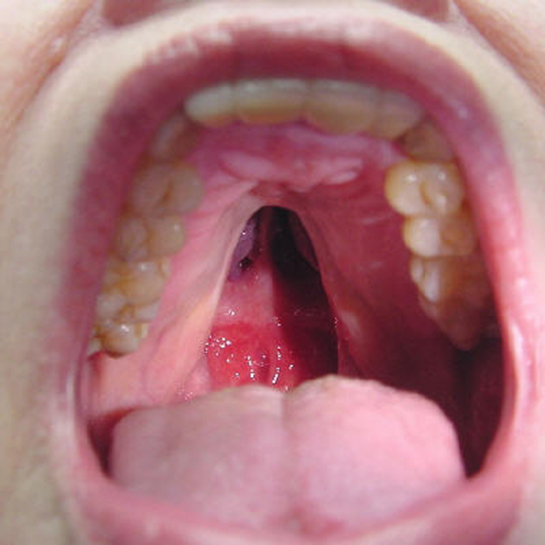

Yaşadığınız üst damakta kabarma durumu gerçekten rahatsız edici olabilir. Bu tür belirtiler alerji, sinüzit veya başka sağlık sorunlarından kaynaklanabilir. Yutkunma zorluğu ve artan ağrı, iltihaplanma veya tahrişin bir işareti olabilir.

Alerji ve Sinüzit Bağlantısı

Alerjik reaksiyonlar, özellikle gıda veya polen gibi maddelere karşı duyarlılığınız varsa, üst damakta şişlik yapabilir. Sinüzit ise burun tıkanıklığı ve yüz ağrısı ile birlikte bu tür belirtilere neden olabilir.

Üst damak şişmesi yaşamanız gerçekten rahatsız edici bir durum. Özellikle öksürük ve nefes darlığı gibi belirtileriniz olduğunda, bu durumun altında yatan sebebin ne olduğunu merak etmek oldukça doğal. Alerjiler, özellikle besin alerjileri, üst damak şişmesine neden olabilir ve bu durumda genellikle yanak ve dilde de şişlikler görülür. Eğer bu belirtiler alerjiden kaynaklanıyorsa, antihistaminikler gibi tedavi yöntemleriyle rahatlama sağlanabilir. Bununla birlikte, sinüzit ya da mononükleoz gibi diğer sağlık sorunları da bu tür şişmelere yol açabilir. Sinüzit, kafa bölgesindeki boşlukların iltihaplanmasıyla ortaya çıkarken, mononükleoz ise Epstein-Barr virüsünden kaynaklanır ve genellikle gençlerde görülür. Eğer bu belirtiler devam ederse, bir sağlık profesyoneline başvurmak en iyisi olacaktır. Bu şekilde, doğru tanı ve uygun tedavi yöntemleri için gerekli adımları atabilirsiniz. Unutmayın, zamanında müdahale etmek her zaman önemlidir.